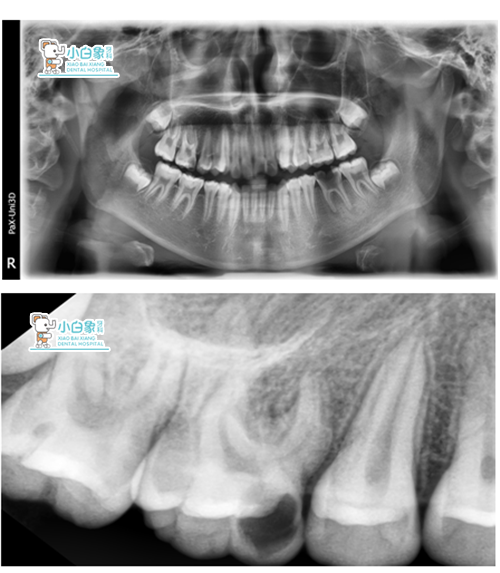

X线:16低密度影像达髓角

36根尖见低密度影像

16死髓牙

36慢性根尖周炎